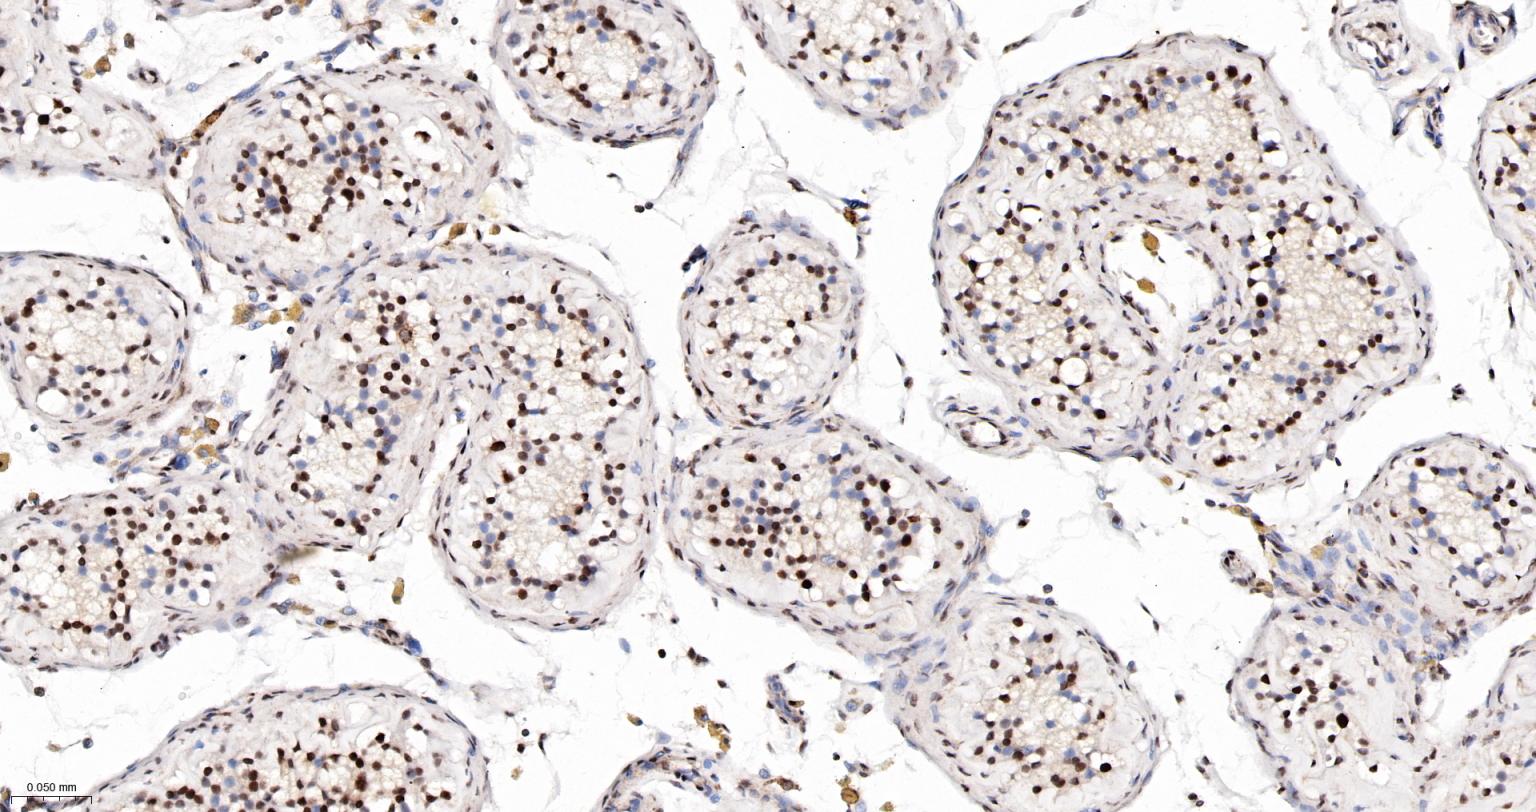

Paraformaldehyde-fixed, paraffin embedded Human Testicles; Antigen retrieval by boiling in sodium citrate buffer (pH6.0) for 15 min; The section was incubated with PRPF19 Monoclonal Antibody, Unconjugated (bsm-61268R) at 1:200 overnight at 4°C, followed by conjugation to the bs-0295G-HRP and DAB (C-0010) staining.